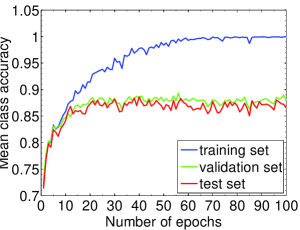

We highlight that training-relevant hyper-parameters can significantly affect the convergence of cost function, the learning speed and the generalization capability of the network. Their impacts are demonstrated via the learning curves of MCA on training, validation and test sets shown from Fig. 4 to Fig. 8. In each figure, we focus on one hyper-parameter while the others are set to their optimal values in Table 2.

Fig. 4 LABEL:sub@subfig:lr1 indicates that when learning rate is small, e.g., , the learning process is so slow that the MCA of the three sets have not become stable in epochs. Properly increasing the learning rate effectively improves learning efficiency and the MCA becomes stable in epochs, as shown in Fig. 4 LABEL:sub@subfig:lr2. At the same time, an over-large learning rate, e.g., , will destabilize the learning process and degrade the classification performance. Also, Fig. 5, 6 and 7 demonstrate the impacts of mini-batch size, momentum and weight decay, respectively.

The evolution of the MCA on test set with the epochs is plotted in Fig. 12. As shown by the line of “No rotation”, CNN-Finetuning does not work well at the beginning. Nevertheless, it catches up quickly in a couple of epochs and reaches a satisfying performance in epochs. Furthermore, the adaption stage is significantly shortened, by applying data augmentation to the small training set of ICPR2012 to increase training samples. These results demonstrate the high efficiency of the adaptability of our CNN-based system, especially considering that there are two different classes of staining patterns across these datasets. Comparison of CNN-Standard and CNN-Finetuning is shown in Table 5. It is interesting to note that CNN-Finetuning consistently outperforms CNN-Standard, even though it is only fine-tuned for a few epochs. We attribute its superiority to the good initialization of the network obtained from the training process on ICPR2014 dataset. Based on the above results, we believe that our CNN-based system will be a better option for practical applications.